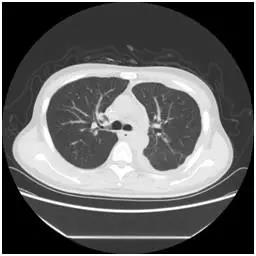

該患者胸部CT(3月9日)